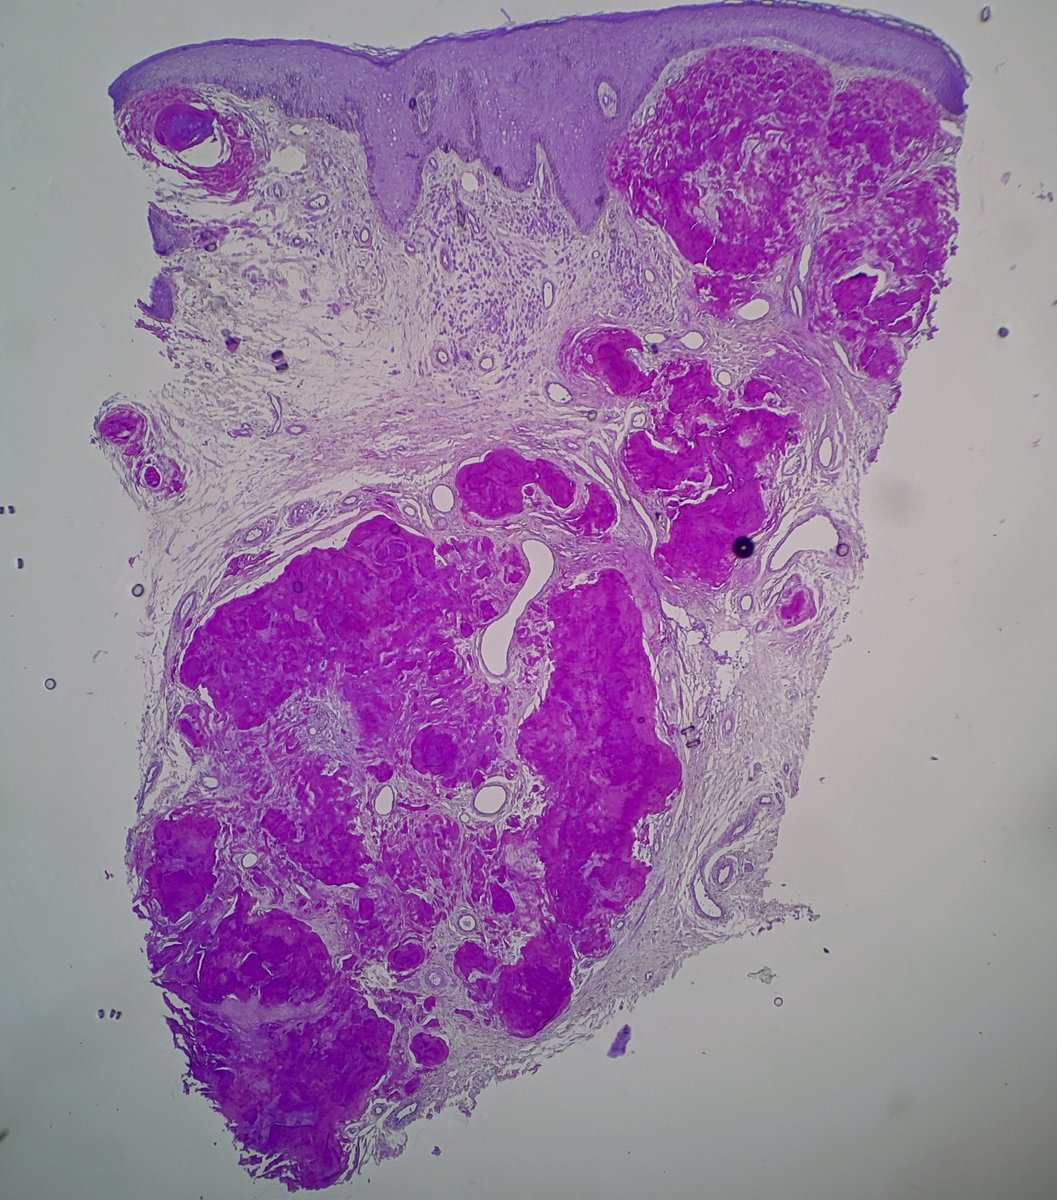

One typical feature of NTRK1 fusion Spitz lesions is a "nest of nests" pattern - what looks like a nest at low power turns out to be smaller nests rammed together at higher power. IHC is pan NTRK. #dermatology #dermpath #pathology